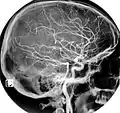

In anatomy, the left and right common carotid arteries (carotids) (English: /kəˈrɒtɪd/[1][2]) are arteries that supply the head and neck with oxygenated blood; they divide in the neck to form the external and internal carotid arteries.[3][4]

The common carotid arteries are present on the left and right sides of the body. These arteries originate from different arteries but follow symmetrical courses. The right common carotid originates in the neck from the brachiocephalic trunk; the left from the aortic arch in the thorax. These split into the external and internal carotid arteries at the upper border of the thyroid cartilage, at around the level of the fourth cervical vertebra.

At approximately the level of the fourth cervical vertebra, the common carotid artery splits ("bifurcates" in literature) into an internal carotid artery (ICA) and an external carotid artery (ECA). While both branches travel upward, the internal carotid takes a deeper (more internal) path, eventually travelling up into the skull to supply the brain. The external carotid artery travels more closely to the surface, and sends off numerous branches that supply the neck and face.